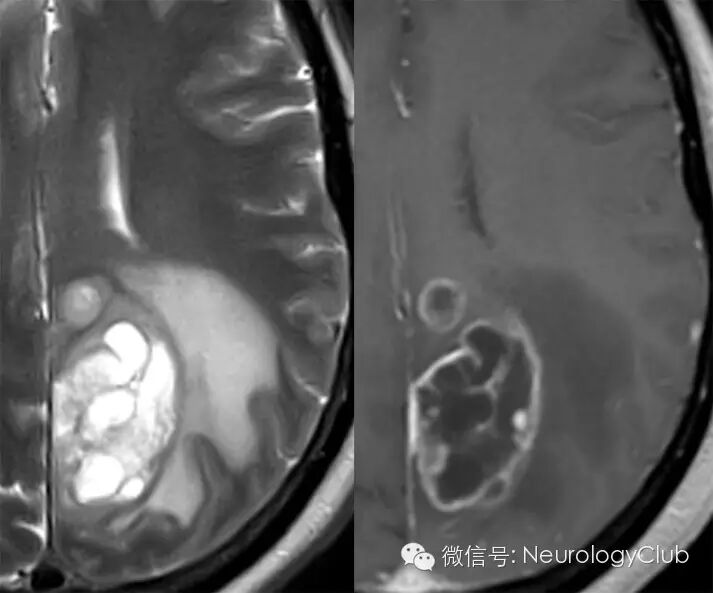

CT显示肿瘤呈边界不清的混杂密度影,常见瘤内出血所致高密度或囊性变、坏死;肿瘤跨胼胝体生长至对侧大脑半球时,呈“蝴蝶征”,水肿和占位效应明显。MRI在一定程度上能够揭示肿瘤的病理改变:T1WI呈不均匀低信号(图 1a),多合并坏死、囊性变或出血性改变;T2WI呈混杂高信号,中心坏死区为高信号,肿瘤生长区周围呈等信号,部分病变与肿瘤周围水肿分界不清,肿瘤内异常血管增生形成线样“流空效应”区(图 1b)。增强扫描肿瘤边缘呈显著对比强化,呈“花环”(ring/rim-enhancing)样(图 1c)、不规则环形、岛形或螺旋形改变;囊变性和坏死区周围肿瘤实质呈特征性“假栅栏征”,即圆形、椭圆形未强化区散在分布在强化区内,类似乳突蜂窝小房。DWI多呈高信号,ADC值明显减低。MRS提示NAA峰降低,Cho升高明显,MI峰较低级别星形细胞瘤低。灌注成像显示,病灶周围和病灶内有多处高灌注区(图 1d),提示大量肿瘤血管生成。胶质母细胞瘤虽具典型影像学特征,但仍需注意与颅内单发转移瘤、间变性胶质瘤、淋巴瘤等肿瘤性病变,以及脑脓肿、结核瘤、脱髓鞘假瘤等非肿瘤性占位性病变相鉴别。

(图5:胶质母细胞瘤囊变)

(图6:CT环形强化)